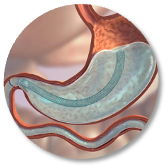

The first cut-free endoscopic treatment for diabesity, ForePass ® is able to replicate the most common types of metabolic surgery (Roux-en-Y Gastric Bypass, RYGB, BilioPancreatic Diversion, and Sleeve Gastrectomy). The first version of our product is aimed at RYGB.

ForePass ® replicates the three most common metabolic surgeries without requiring a single cut